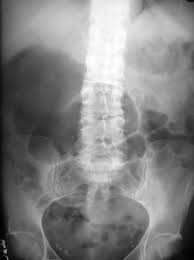

The patients symptoms resolved quickly after colonoscopic reduction and elective laparoscopic surgery was performed 18 days after admission. A planned surgery is not fun but an emergency surgery for a twisted colon would be even worse. Based on these findings we diagnosed cecal volvulus caused by mobile cecum syndrome. On the other hand a chronic form of mobile cecum syndrome which is the most common form reported a history of intermittent crampy abdominal pain distension and constipation. However it may be present as a precursor of frank cecal volvulus in approximately 50 per cent of the cases. 102 patients were followed up to 15 years after the operation. Abstract Five cases of mobile cecum syndrome are presented. Ehlers-Danlos syndrome hypermobility type EDS-HT mobile cecum ptosis laparoscopic. The following symptoms may be experienced with cecal volvulus.

On the other hand a chronic form of mobile cecum syndrome which is the most common form reported a history of intermittent crampy abdominal pain distension and constipation. It lies at the junction of the small and the large intestines and is the origin of the appendix. Ballooning abdomen abdominal distension. Thats about as mobile as you can get. The following symptoms may be experienced with cecal volvulus. A mobile caecum and ascending colon is a rare congenital abnormality. The cecal volvulus represents the acute form with typical feature of a bowel obstruction that needs immediate operative treatment.